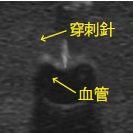

パッドは、超音波ガイド下で穿刺でき、カテーテルの挿入が可能な新素材を使用。

超音波ガイド下穿刺では、初学者がわかりやすい鮮明な画像を得ることが可能。